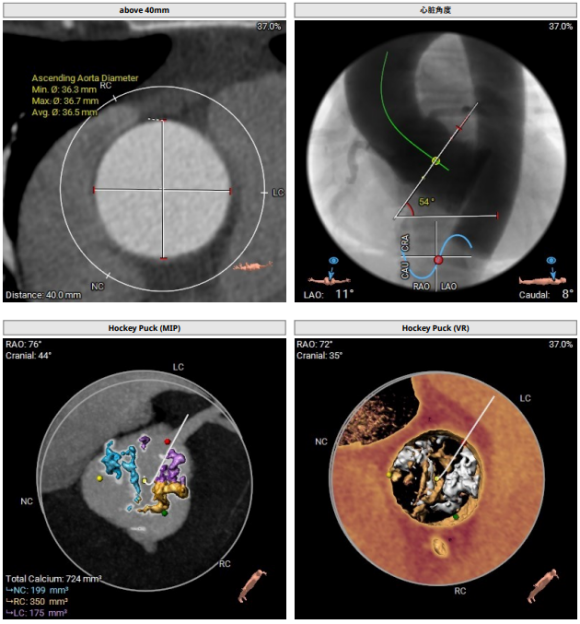

主动脉根部:功能型二叶瓣,瓣叶增厚,重度钙化,左右可见钙化融合。左冠开口高度约14mm,右冠开口高度约15.4mm。法式窦结构大,STJ高度约20.2mm、直径约30.6mm。升主动脉未见明显扩张,心脏角度约54°。左室大小尚可,心肌增厚。CT显示患者结构偏大,瓣环及流出道成敞口状。瓣上各辅助锚定区域处于临界值,给手术操作带来挑战。 请注意,我没有改变原文的意思。

功能型二叶瓣,瓣叶增厚,重度钙化,左右可见钙化融合,左冠开口高度约1 4mm,右冠开口高度约1 5.4mm,法式窦结构大,STJ高度约20.2mm、直径约30.6mm,升主动脉未见明显扩张,心脏角度约54°,左室大小尚可,心肌增厚。CT显示患者结构偏大,瓣环及流出道成敞口状,瓣上各辅助锚定区域处于临界值,给手术操作带来挑战